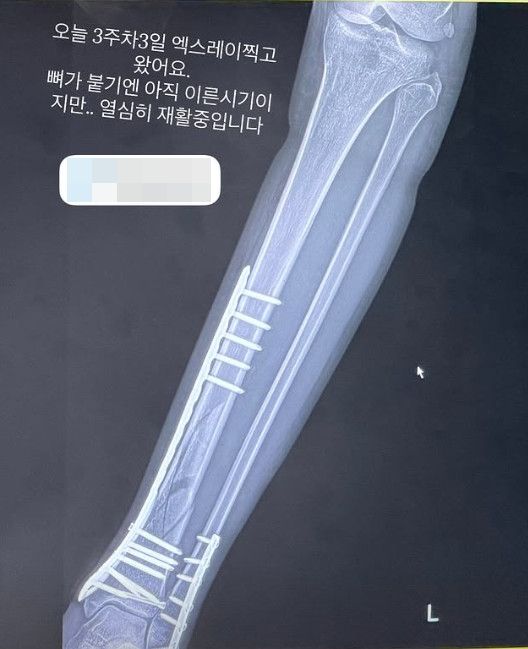

(엑스포츠뉴스 정연주 기자) 엄지원이 발목 수술 후 회복 근황을 전했다.

지난 12일 엄지원이 자신의 SNS에 엑스레이 사진을 공유했다. 엄지은 "오늘 3주차3일 엑스레이 찍고 왔어요. 뼈가 붙기엔 아직 이른시기지만... 열심히 재활중입니다"라는 멘트와 함께 재활 사실을 알렸다.